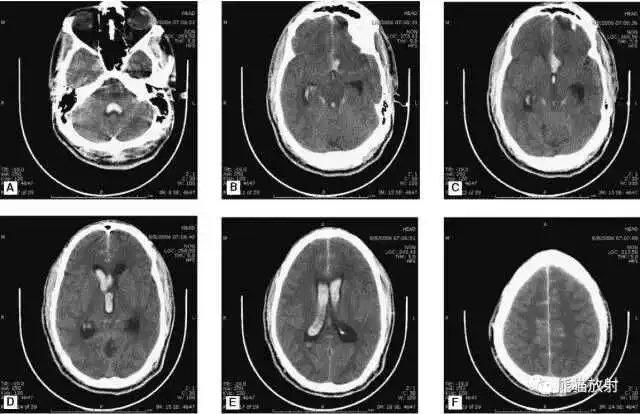

缺血性脑卒中

- 早期:脑水肿,灰白质分界模糊,脑沟消失;

- 中期:病变区域密度减低;

- 晚期:脑实质体积缩小。

A:陈旧性脑梗死,右枕叶体积缩小;

B:左枕叶急性脑梗死,灰白质分界模糊,脑沟消失;

另一患者:

C、D:亚急性期脑梗死,低密度,无明显占位效应。

▲

左侧大脑中动脉供血区脑梗死(亚急性期):

低密度,轻度水肿

缺血性脑卒中发作2-4天时,占位效应最明显。